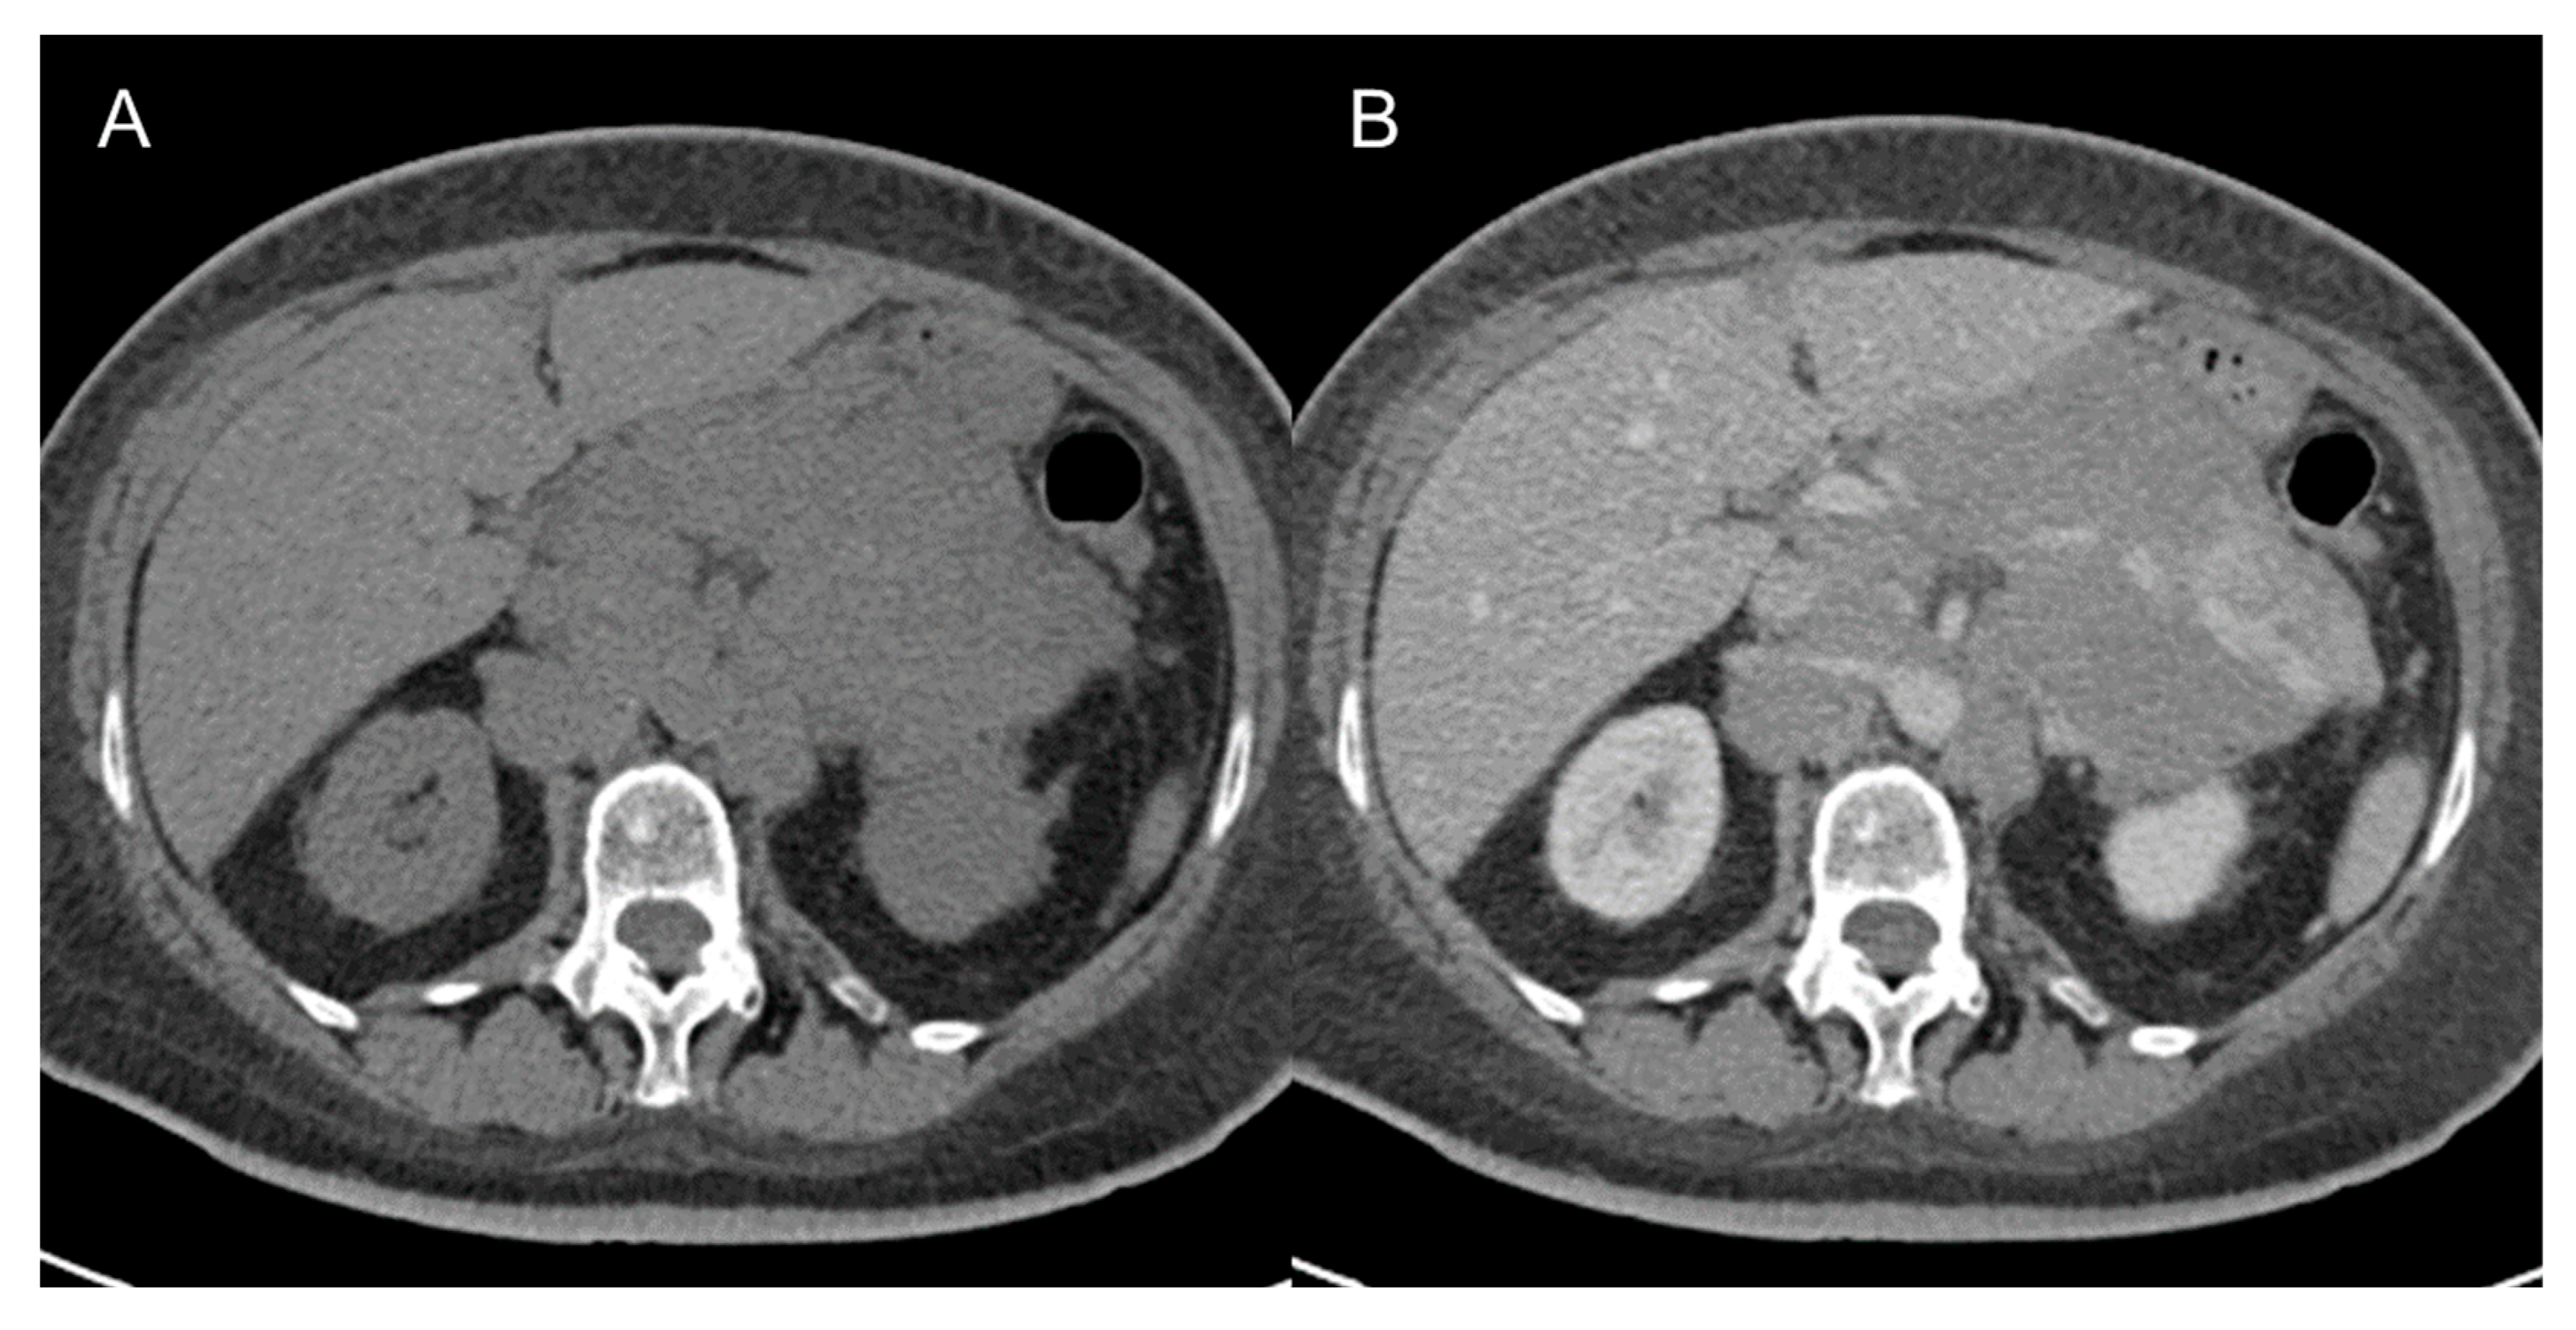

The main differential diagnosis is with simple lipomas (Figure 3) that will present as purely adipocytic tumors [38]. In this case, when the lesion is ≤10 cm, the patient can be managed without a biopsy. Beyond 10 cm, patients should still undergo MRI and biopsy [9]. Another diagnosis to keep in mind is renal angiomyolipoma, which, contrary to LPS, is hypervascular and presents with a large vessel extending into the renal cortex. Moreover, the presence of a renal parenchymal defect at the site of tumor contact favors exophytic angiomyolipoma. Other rarer occurrences to consider are adrenal myelolipomas, which share similar imaging appearance with angiomyolipoma, and ovarian teratomas. Features that should favor the latter are the presence of fat–fluid levels or tooth-like calcifications [38].

Figure 3.

Abdominal lipoma in a 67-year-old man. Axial (A) and coronal (B) contrast-enhanced CT images in the venous phases show a 6.8 cm fatty mass (arrow) in the right abdominal wall, with no internal septa or nodules.

LMS is a smooth muscle tumor [38], more common than LPS in younger age groups [6]. Its most frequent location is the retroperitoneum, near the inferior vena cava [43]. LMS are heterogeneous masses (Figure 4), with irregular peripheral enhancement and enhancing solid portions, mixed with cystic, hemorrhagic, or necrotic areas. LMS show marked T2 hypointensity on MRI and are similar in attenuation to uterine myometrial smooth muscle on CT [39]. Fatty components and calcifications are usually absent [34,38]. The evidence of a large, heterogeneously enhancing, necrotic retroperitoneal mass contiguous with a vessel, with extra- and intraluminal involvement, is highly suggestive of LMS [12,37,43]. It could stem from the inferior vena cava, extending into the intrahepatic portal veins or superior mesenteric vein, or even from small vessels such as renal or gonadic veins. Differentiation from extrinsic compression can be challenging [12,40].

Figure 4.

Retroperitoneal leiomyosarcoma in a 63-year-old woman. Axial (A) and coronal (B) CT images on venous phase show a 10.2 cm heterogeneous mass with central area of low attenuation consistent with necrosis (arrow).